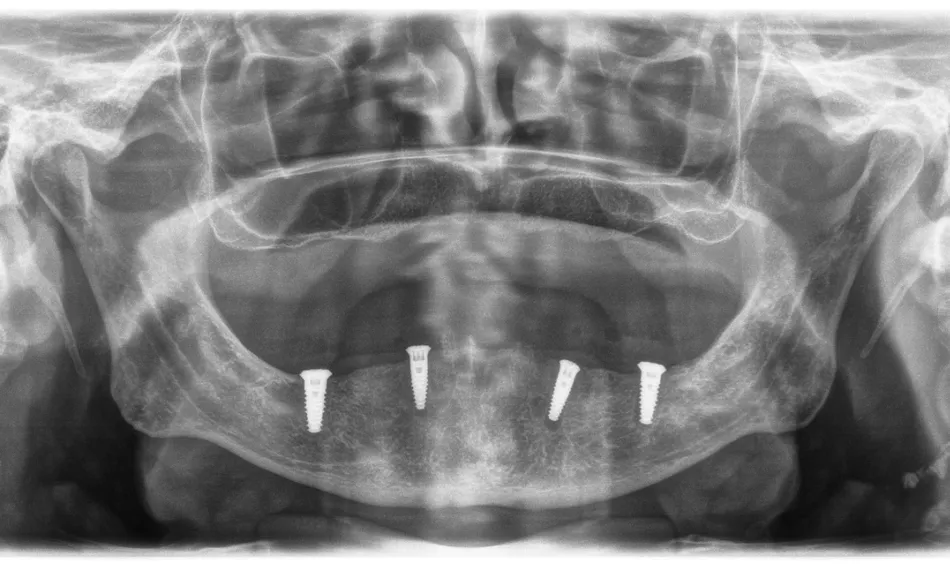

A control radiograph was taken (Fig. 19).

Fig. 19